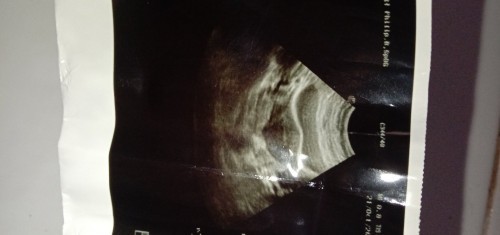

Butuh pelukan bun 😭😭Baru pulang dari dokter.. kata dokternya kandungannya sudah luruh.. pantes kemaren perut terasa sakit banget.. dalam semalam ganti pembalut sampe 4x karna saking banyaknya darah yang keluar.. uk 7 minggu